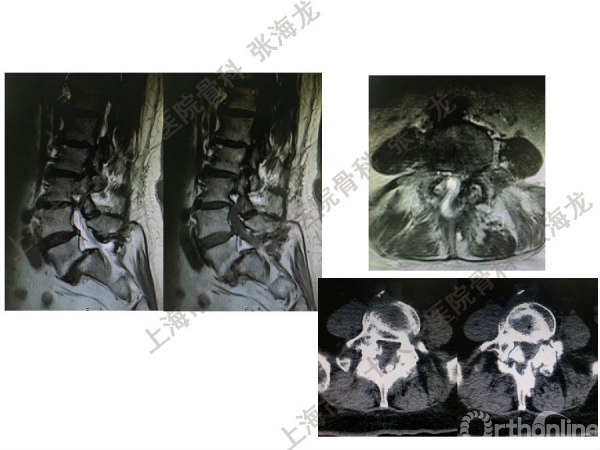

2008年3月至2010年8月,上海市第十人民医院骨科随访49例腰椎滑脱症(峡部裂型和退变型)患者,对比23例微创手术MIS-TLIF和26例开放手术治疗腰椎滑脱症的临床及影像学结果,进行了回顾性研究。

研究发现,Wiltse入路Mis-TLIF更直接的暴露峡部及关节突,对脊柱稳定性的影响较小;彻底松解辅助双重提拉复位Mis-TLIF,对于峡部裂型滑脱有较好的复位效果;对于峡部裂型滑脱,提拉复位在影像学参数上有一定优势;与原位融合相比,ODI.VAS.JOA无明显差异(样本量有限);对于退变性滑脱,单纯撑开椎间隙与原位融合可以获得较好疗效。